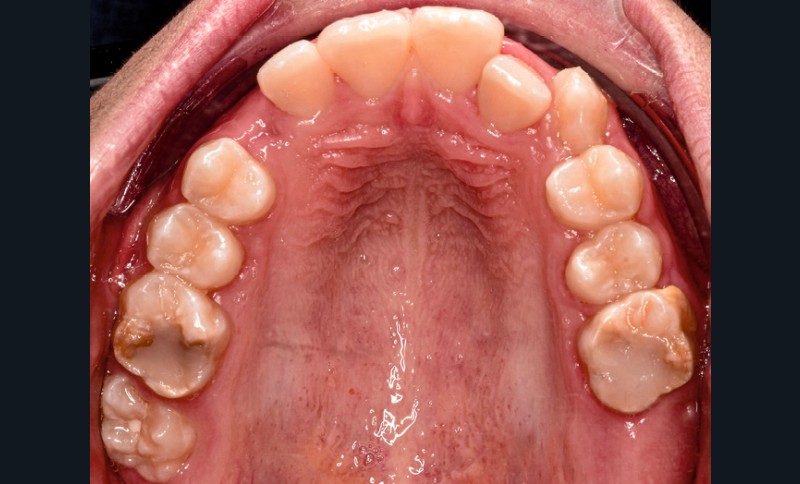

Fares, 13 ans, est adressé par son dentiste pour un bilan orthodontique dans le cadre d’une Hypominéralisation Molaire-Incisive (MIH). L’enfant est en bonne santé générale.

La MIH est une anomalie qualitative de l’émail affectant une à quatre premières molaires permanentes, souvent associée aux incisives. Elle se manifeste par des opacités bien délimitées, de teinte blanche à brunâtre, avec une fragilité amélaire pouvant entraîner des pertes de substance post-éruptives, une hypersensibilité et une susceptibilité accrue aux caries.

L’étiologie est multifactorielle et partiellement élucidée. Trois formes sont décrites : légère (opacités sans perte de substance), modérée (opacités pigmentées et sensibilité) et sévère (perte tissulaire, effondrement post-éruptif, restaurations atypiques ou extractions) [1].

L’examen clinique montre une MIH sévère sur 16, 26, 36 et 46, et modérée sur 11 et 21.